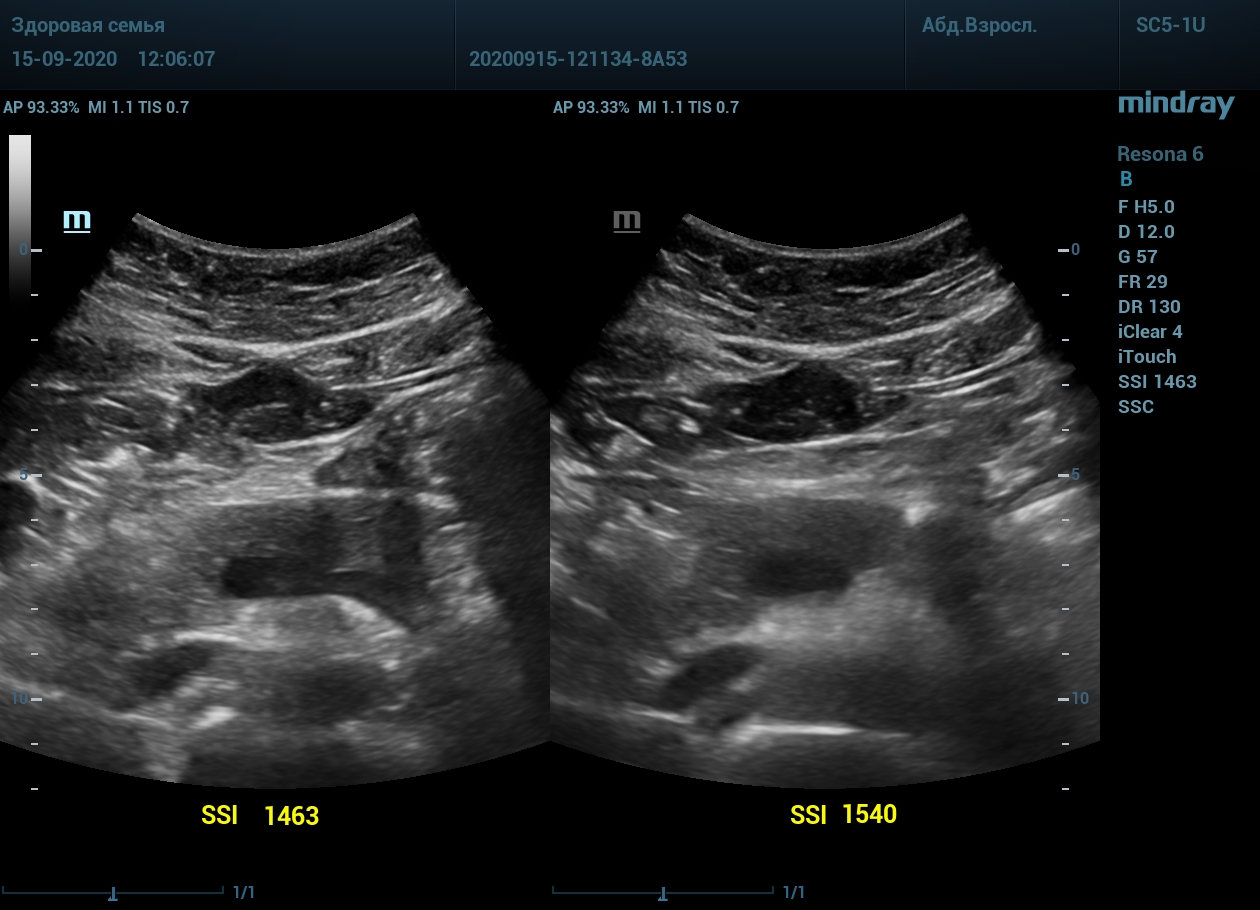

2. Абдоминальный доступ левой почки. После калибровки скорости, дальний от датчика контур почки становится четким и контрастным.